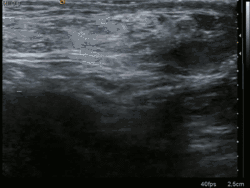

Medical imaging

A physician may diagnose an inguinal hernia, as well as the type, from medical history and physical examination.[20] For confirmation or in uncertain cases, medical ultrasonography is the first choice of imaging, because it can both detect the hernia and evaluate its changes with for example pressure, standing and Valsalva maneuver.[21]

When assessed by ultrasound or cross sectional imaging with CT or MRI, the major differential in diagnosing indirect inguinal hernias is differentiation from spermatic cord lipomas, as both can contain only fat and extend along the inguinal canal into the scrotum.[22]

On axial CT, lipomas originate inferior or lateral to the cord, and are located inside the cremaster muscle, while inguinal hernias lie anteromedial to the cord and are not intramuscular. Large lipomas may appear nearly indistinguishable as the fat engulfs anatomic boundaries, but they do not change position with coughing or straining.[22]